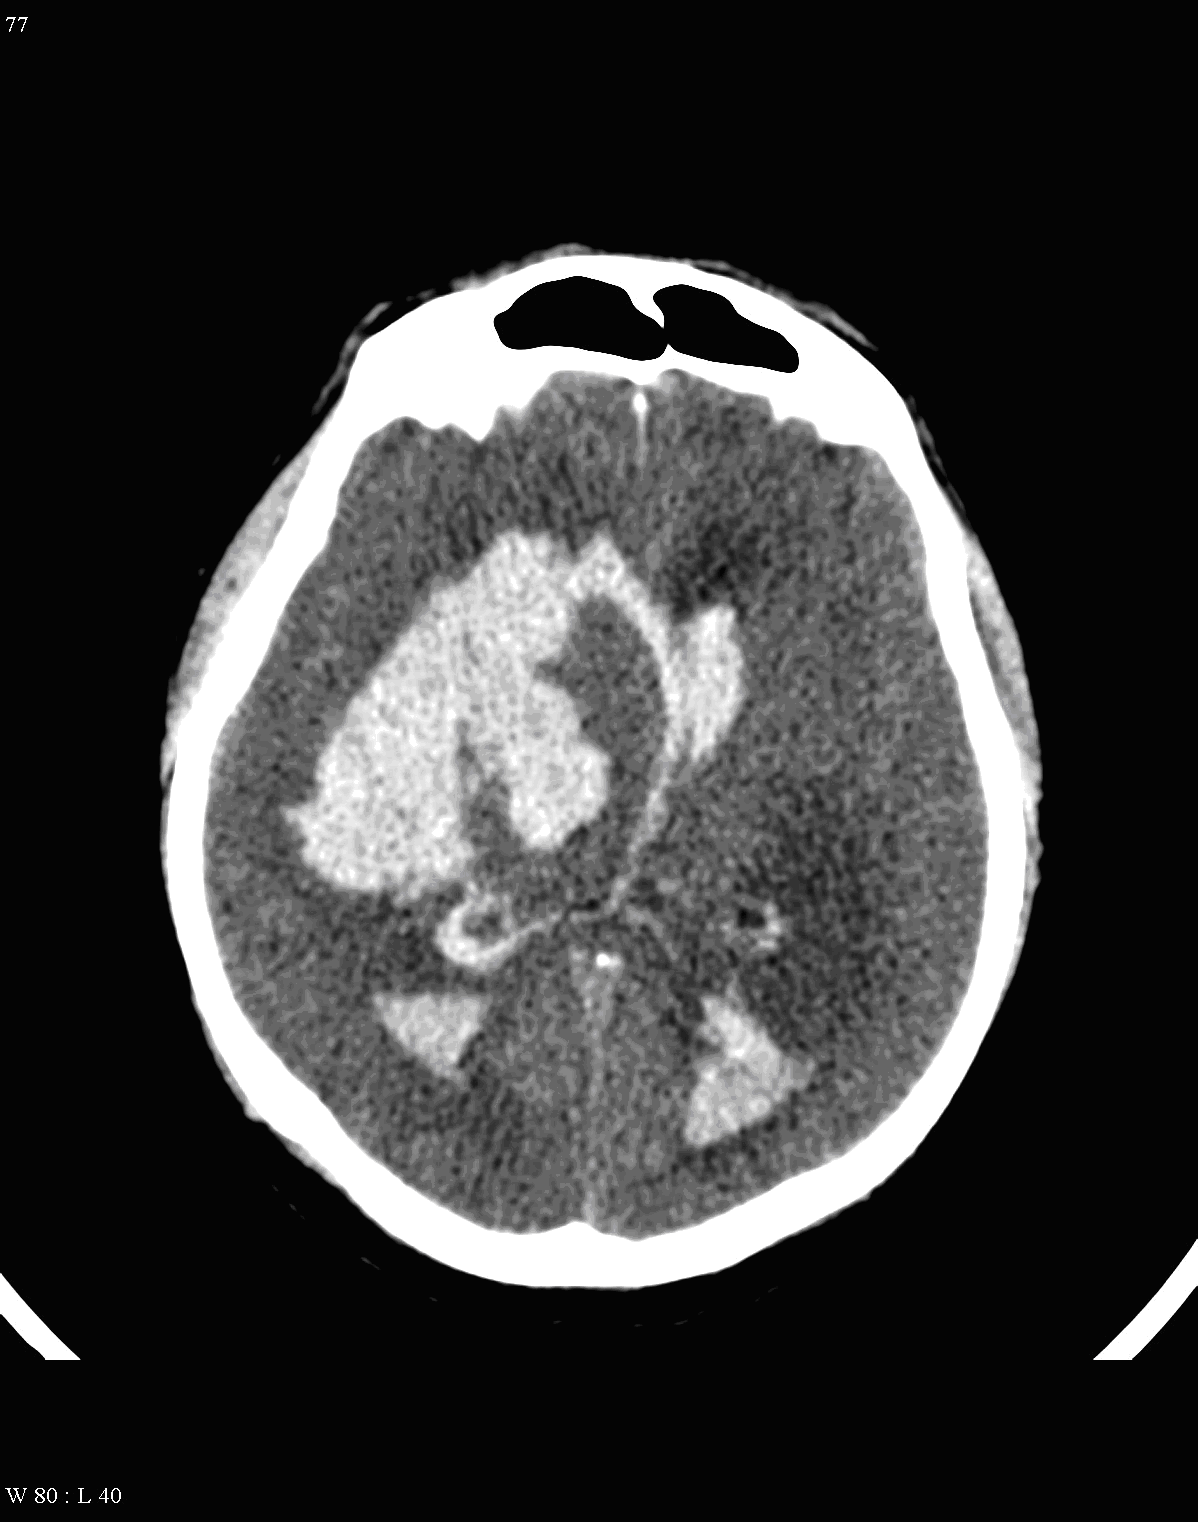

Image

10a: Right thalamic hemorrhage and bleeding in the 3rd ventricle,

10b: Right lobar hemorrhage with ventricular bleeding

On CT images acute bleeding always presents as hyperdensity. (One has to keep it mind that hyperdensity of the blood is affected by the hematocrit levels, hence making the diagnosis more difficult.) Intraparenchymal blood is dominated by a destructive appearance (mass-effect) and it is surrounded by hypodensity as a sign of perifocal edema. It often breaks into the ventricles. In patients lying in a supine position they collect (sediment) at the occipital horn of the lateral ventricles, creating a hyperdense liquid-to-liquid levels. Later on, the density of blood decreases and shows a peripheral ring or rim-like contrast enhancement without mass-effect.